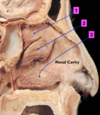

Identify 2

Hard Palate

Identify 4

Vestibule of Oral cavity

NB: Oral cavity Proper = Posterior to teeth

Identify 5

Maxillary Teeth

Identify 7

Mandibular Teeth

Identify 8

Genioglossus Muscle

Identify 9

Geniohyoid Muscle

Identify 10

Digastric Muscle

(Ant. belly of)

Identify 11

Mylohyoid Muscle

Identify 12

Hyoid Bone

Identify 13

Nasopharynx

Identify 14 (x2)

Soft Palate & Uvula

Identify 15

Oropharynx

Identify 16 (x2)

Lingual Tonsil (& root of tongue)

Identify 17

Laryngopharynx

Identify 18

Epiglottis

Identify 19

Ary-Epiglottic Fold

Identify 20

Laryngopharynx

(Continuous with Oesophagus)

Identify 21

Larynx